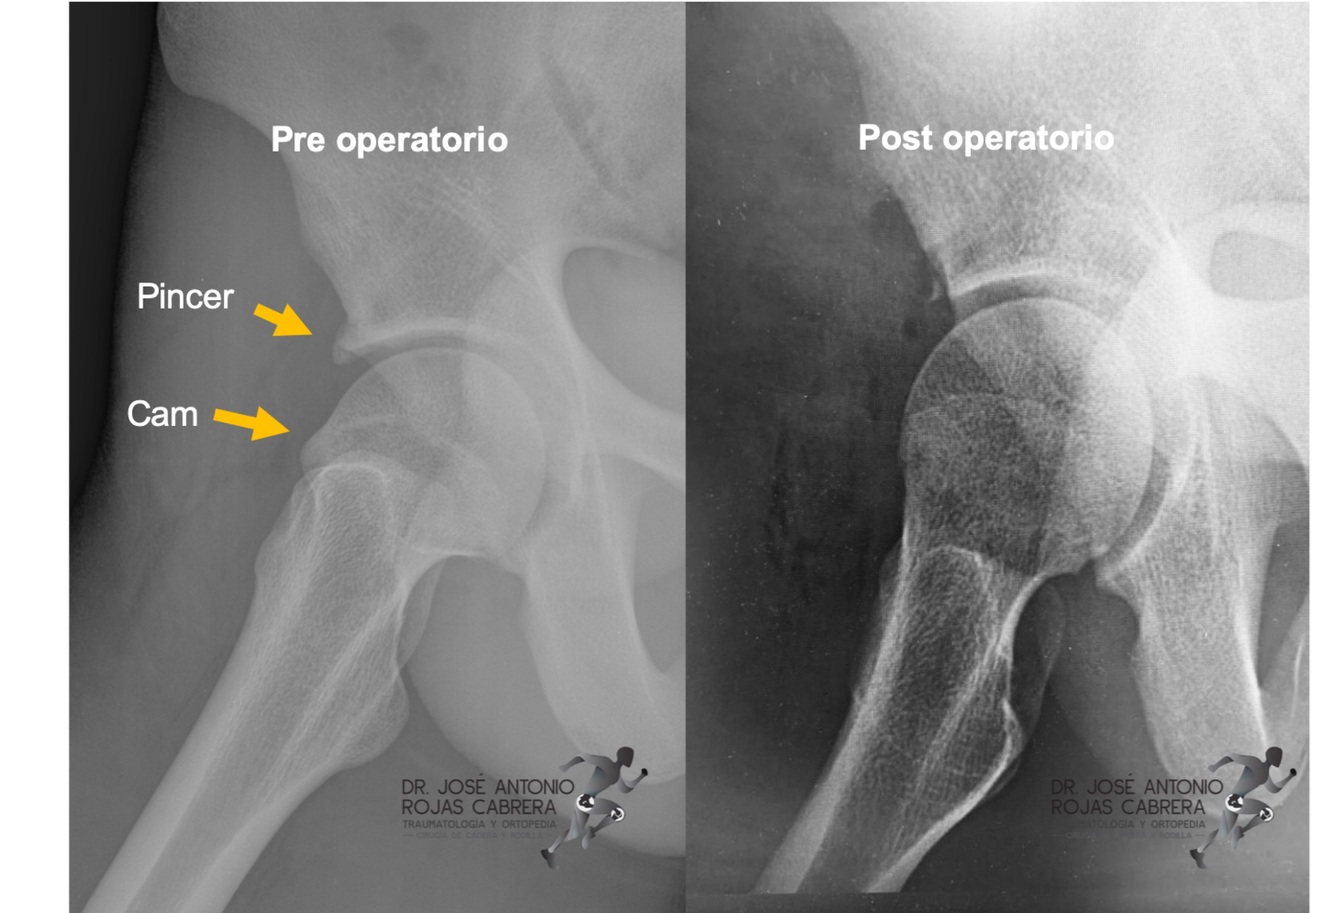

CAM: deformidad cuello femoral

PINCER: sobrecobertura del acetabulo

CAM: + en hombres jovenes

PINCER: mujeres

CAM

PINCER

MIXED